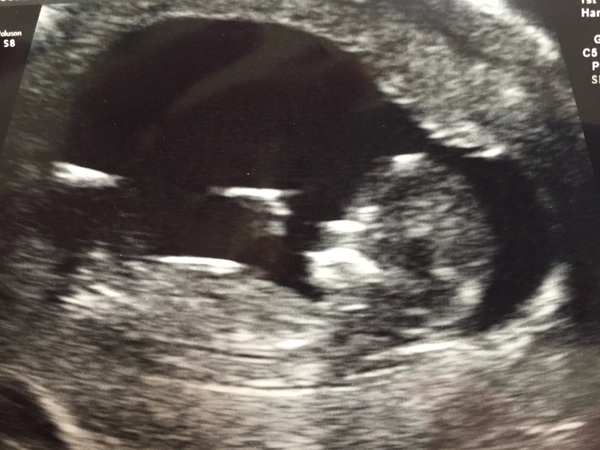

Forgot to say, that in the pic mini monster has got his/her legs crossed like a little Buddha!

FluffyPickleMonster bless. The sonographer pointed out baby bigfam did that at my scan as well, maybe it's comfy Grin

We had a scan at 6 weeks to make sure it wasn't another ectopic, then a reassurance scan at 10 weeks. Finally made it to official dating scan as well. Smile Nearly 14 weeks now and baby was very wriggly. It kept doing somersaults and it was quite difficult to do any measurements. (Managed eventually, though, and luckily all came back low risk.)

Glad that I don't have the only poorly behaved bean. It wasn't keen on having pictures taken at all. (It had been so serene at the 10 week scan and merely leasurely waved at us...)

Very wriggly and uncooperative so had to do some jumping and jiggling to get it in the right place for measurements. All low risk though :)